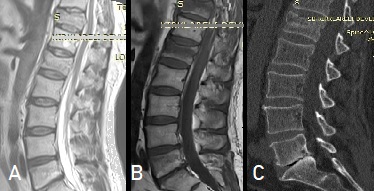

(Direkt

grafi, BT ve MRG incelemelerinde T11 ve L1 vertebralarında yükseklik

kaybı görülmektedir. T11'deki yükseklik kaybı daha belirgin ve %50'ye

yakındır. BT kesitleri T11 seviyesini içermemektedir. Üst ortadaki (B)

T1 sekanslı MRG incelemesinde L5 vertebra korpusu üst yarısında da

kırık olabilecek bir hipodansite vardır. İncelemede STIR sekansları

eksiktir).